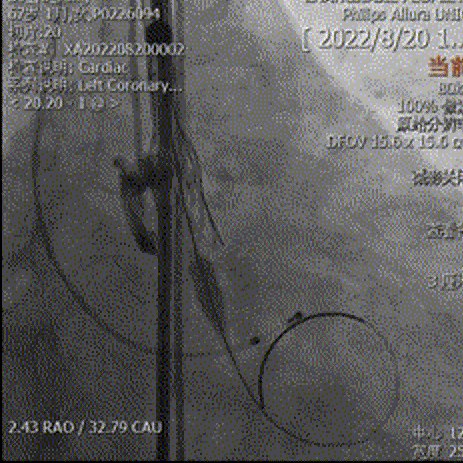

主动脉根部造影可见钙化影,采用18mm球囊预扩,有轻微腰征,无造影剂渗漏,左冠显影正常。

主动脉根部造影

球囊预扩